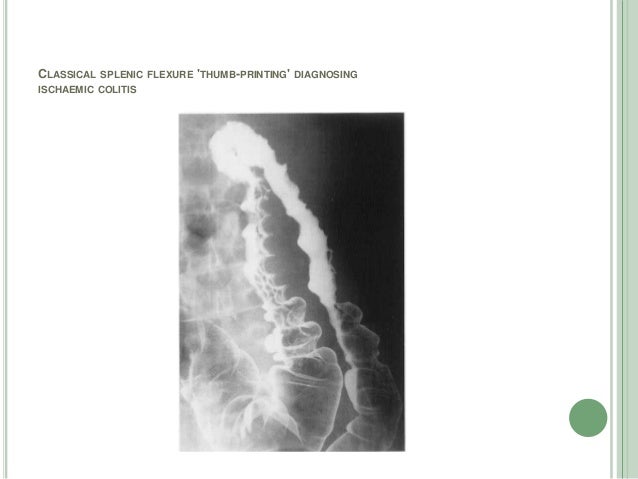

Thumb Printing Sign Ischemic Colitis

Thumbprinting In Ischemic Colitis Nejm